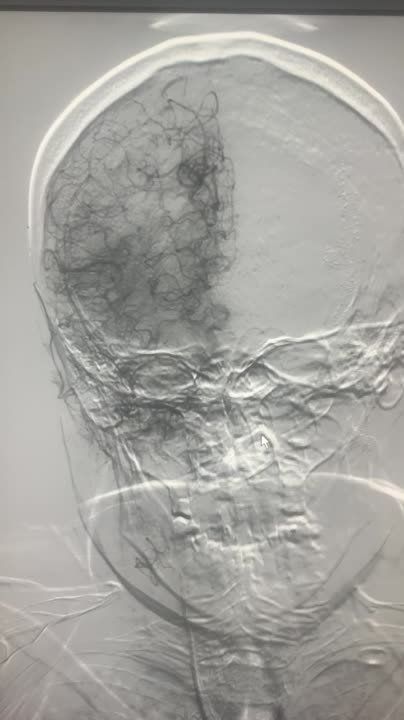

В ДНР спасли женщину с острым нарушением мозгового кровообращения

В ДНР спасли женщину с острым нарушением мозгового кровообращенияСпециалисты Донецкого клинического территориального медицинского объединения (ДОКТМО) в торакальном отделении №2 удалили лёгкое пациент